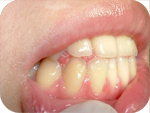

據統計,國人九成以上都有牙周病。牙周病是個很廣泛、大量使用的名詞,現代人解讀的是:只要牙周有問題,都說是牙周病,基本上不論對錯,還算是可以理解的範圍。比較精確的來說,通常是先有牙齦炎,在沒有醫療控制和好好的自我清潔下,就會變成牙周病。牙齦炎最初的症狀就是流血,想必很多人都有刷牙流血的經驗,這就是牙齦炎的表徵,此外牙齦顏色紅腫也可以看的出來跟健康的情況不同。牙周病的具體現象就是牙齦萎縮劇烈,牙齒動搖,無法施力咬,牙周囊袋過深(通常是大於5mm),骨頭吸收,時常覺得口內有異味卻都清不乾淨。經由牙醫師的視診、觸診、X光檢查,就可以判定有無牙周病。

很多人都有牙齦萎縮的問題,牙齦萎縮的原因有幾個:生理性萎縮、刷牙過度用力、牙周病萎縮。當發生這樣的情況時,首先要先瞭解病因為何?生理性萎縮是因為年紀老化的關係,幾乎人人無法避免,只能盡量清潔;如果是刷牙過度用力的,就要改善刷牙方式,調整力道或改用音波電動牙刷;如果是牙周病萎縮的,就要予以治療。但可惜的是:已經萎縮的部分通常不會再長回來,醫師能作的就是把牙齦裸露的地方予以樹脂充填保護。有些美觀區,若是在意的話,就要評估牙周整型手術(取牙齦補牙齦),期待它能恢復可接受的美觀。